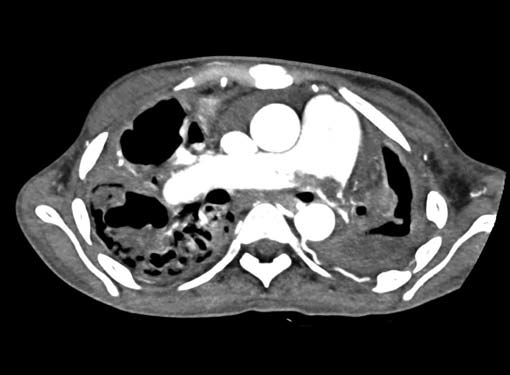

Filling defects (Figs 16A and B) may be seen in main

pulmonary artery (MPA), left pulmonary artery (LPA) and

right pulmonary artery (RPA), interlobar artery, segmental

divisions (Figs 17A and B). On occasions, detection in distal

On occasions, thromboembolism can also be seen in right

ventricle and less commonly in pulmonary veins. Systemic

vein thrombus (innominate veins, SVC, IVC) sometimes

accompanies pulmonary thromboembolism (Figs 18A and B).